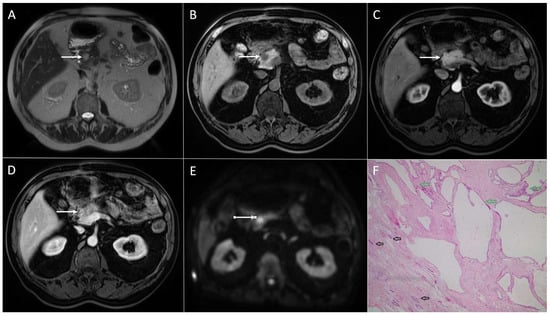

4.1. Serous Cystadenoma

4.2. Mucinous Cystic Neoplasm

4.3. Walled-Off Necrosis

4.4. Cystic Neuroendocrine Tumors